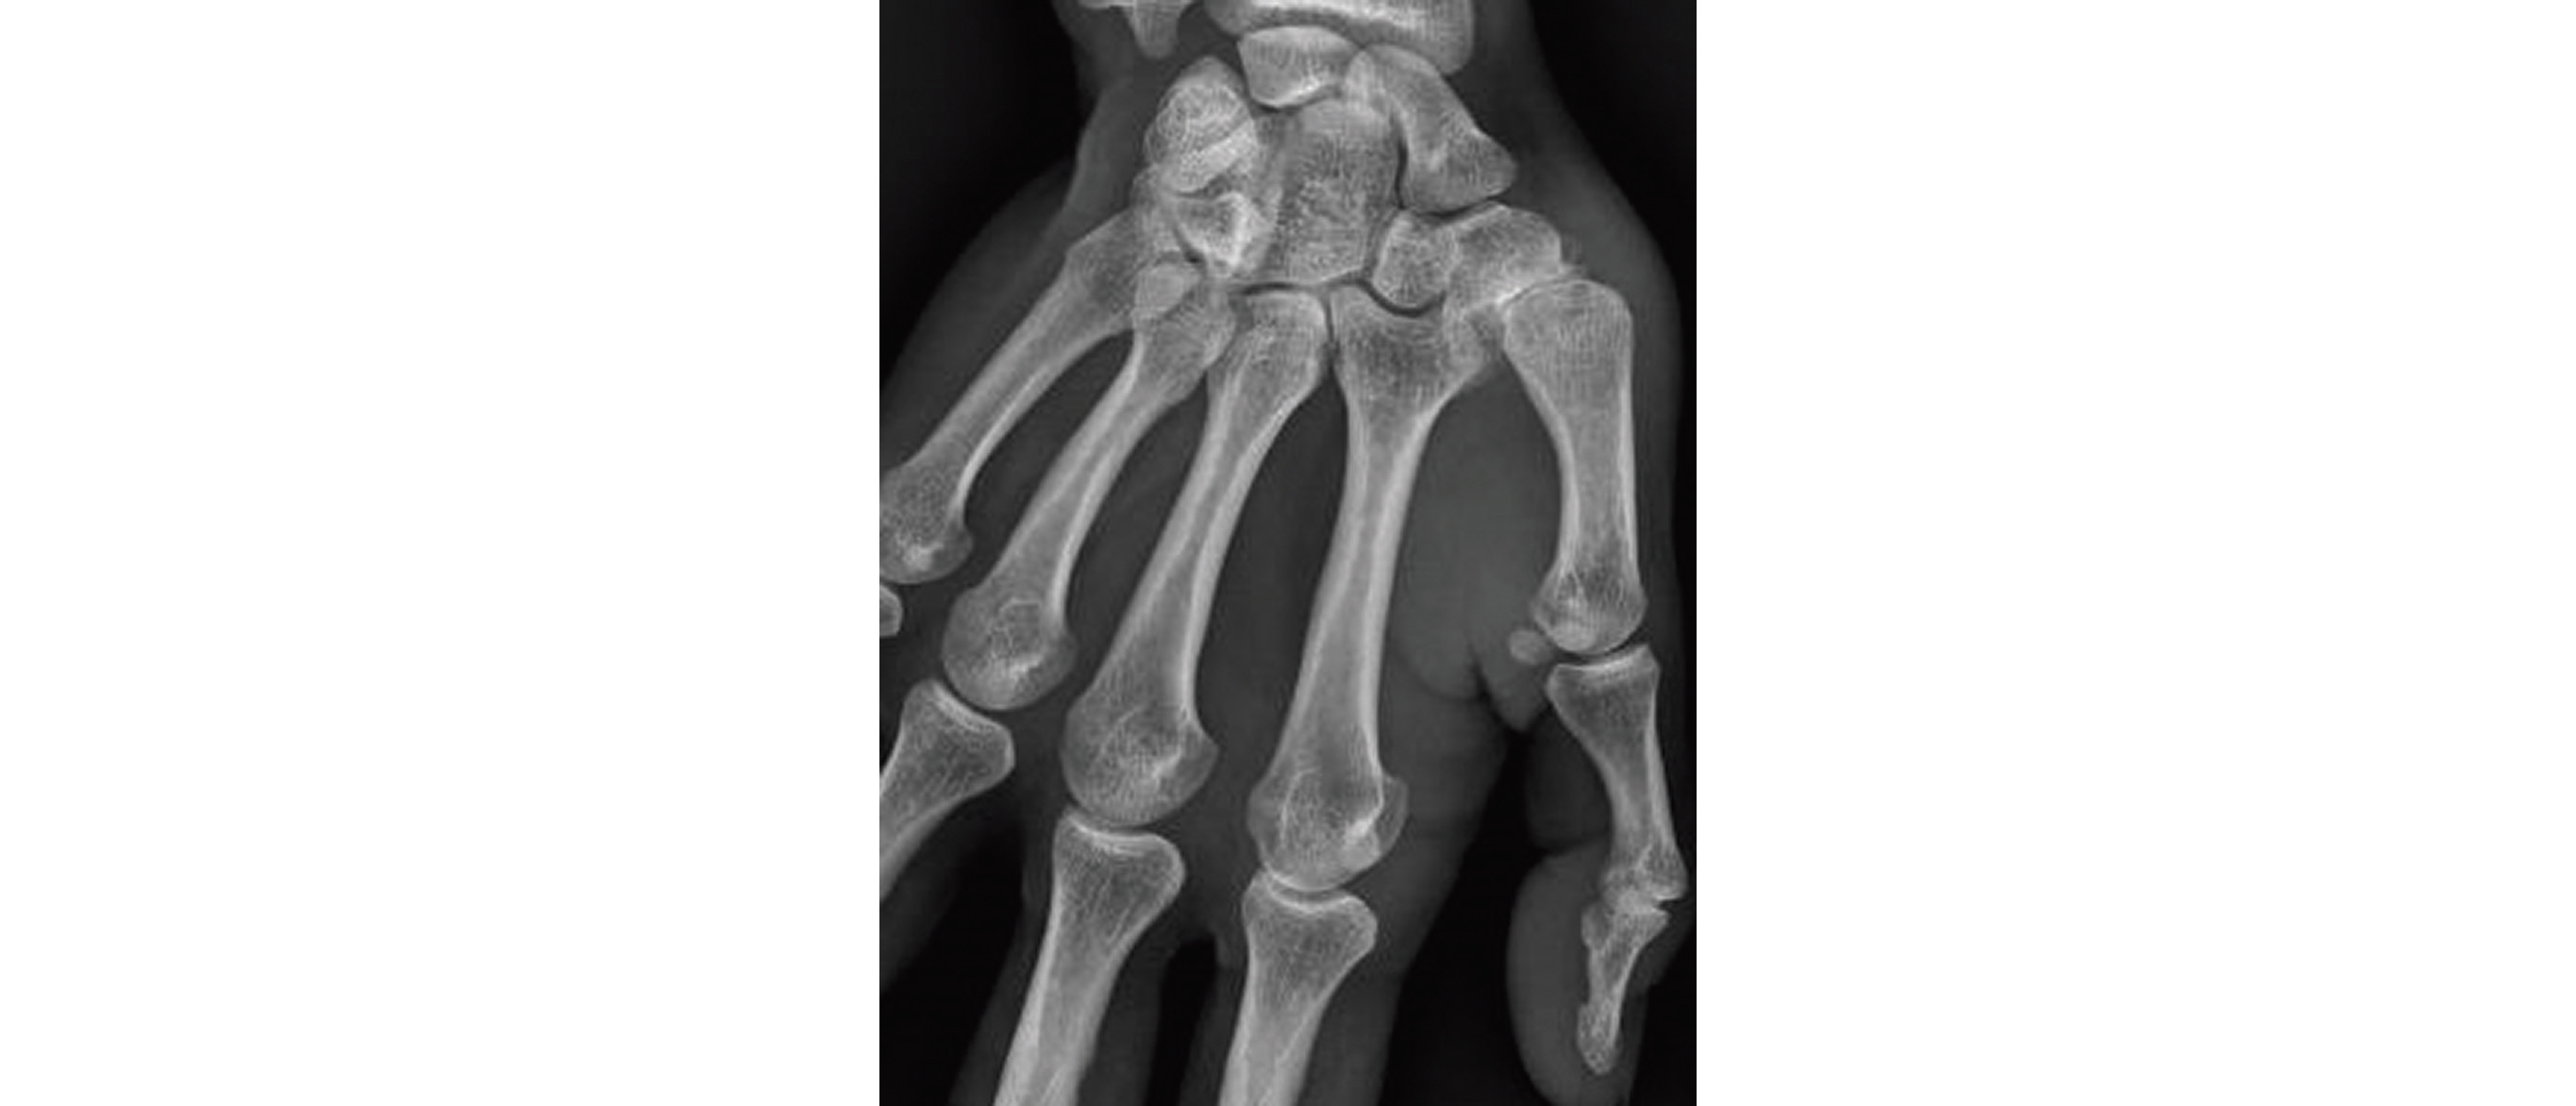

Douleur de la base du pouce sur rhizarthrose

La rhizarthrose ou arthrose trapézo-métacarpienne, est l'arthrose de la base du pouce, c'est une atteinte très fréquente et souvent bilatérale. Douleur, déformation et limitation fonctionnelle en sont les principales plaintes.

Aucun examen complémentaire n'est nécessaire au diagnostic, si des radiographies sont réalisées on retrouvera les signes radiologiques d'arthrose : pincement de l'interligne articulaire, géodes, condensation et ostéophytes.

Arthrose trapézo-métacarpienne

chez une patiente de 70 ans.